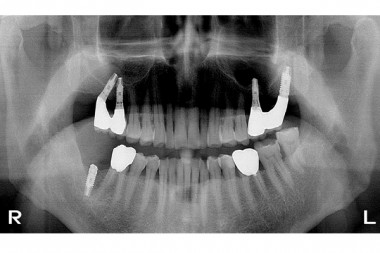

임플란트119 | 상악 양측 구치부 임플란트 제거후 재식립과정 파노라마 사진.

기존 임플란트 제거 및 재식립 과정 입니다.

상악 우측 임플란트 제거 ▼

상악 우측 임플란트 식립  ▼

상악 우측 완성 및 좌측 임플란트 제거  ▼

상악 좌측 임플란트 식립  ▼

상악 좌측 임플란트 완성  ▼